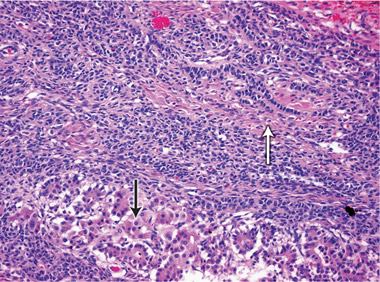

At 59 years of age, a laparotomy was performed and the patient was found to have a large left adnexal mass (Box 1, A) and a normally formed uterus. The mass was removed and a subtotal hysterectomy performed as there was no distinct lower margin of the cervix (Box 1, B). The patient was informed of the operative findings and the diagnosis of intersex. Peripheral blood karyotyping showed a 46,XY genotype. The histopathology of the gonadal tumour showed a sex cord-stromal tumour of indeterminate differentiation (Box 2). The histopathology of the uterus showed simple endometrial hyperplasia. The patient was treated with postoperative chemotherapy, but died 18 months later.

The risk of malignancy in dysgenetic gonads is significantly increased in some patients with DSD.8 The presence of the SPY gene on the GBY region of the Y chromosome is a prerequisite for malignant transformation.9 Tumours can arise in any of the gonadal cells or their precursors.8 Precursor lesions for the development of cancers occur as carcinoma-in-situ in testicular tissue and gonadoblastoma in undifferentiated gonadal tissue. A number of malignant tumour types may occur in dysgenetic gonads.8,10 These include germ cell tumours and sex cord-stromal tumours. Patients presenting with abdominal tumours in dysgenetic gonads in adulthood provide histopathologists with complex diagnostic dilemmas. Histopathological examination of the tumour in our case showed mixed elements, with cells resembling ovarian follicles, testicular tunica, granulosa cells, Sertoli cells and Leydig cells. No germ cell components were identified. The final consensus was a diagnosis of malignant sex cord-stromal tumour of indeterminate differentiation.